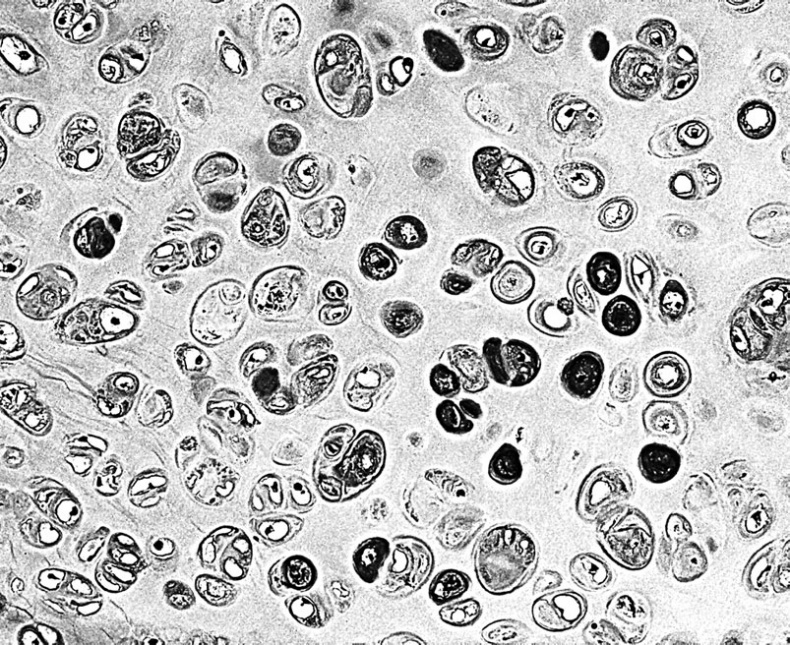

2. Соединительная ткань, играющая вспомогательную роль во всех без исключения, органах, где она выполняет опорную, защитную и трофическую (питательную) функции. Соединительная ткань образует опорный каркас и наружные покровы всех органов. Соединительная ткань отличается большим разнообразием клеток, к ней относятся кровь и кроветворная ткань, лимфатическая ткань, жировая ткань, костная ткань, хрящевая ткань, волокнистая соединительная ткань. Клетки соединительной ткани расположены рыхло, в ней много межклеточного вещества.

Кровь